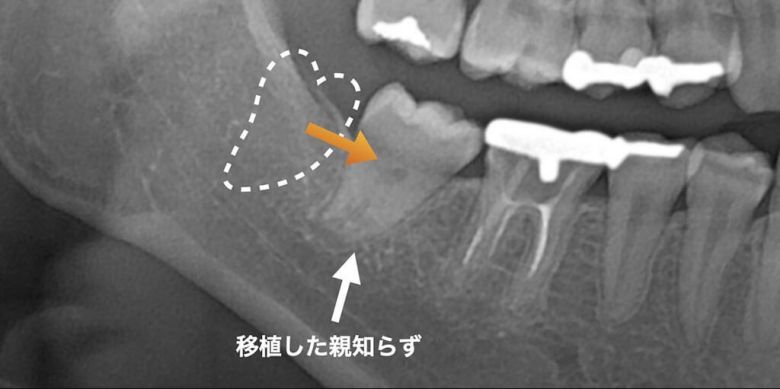

例えば一本抜かないといけない歯があって、その奥に親知らずが埋まっているという場合、親知らずを移植するという方法があります。移植の適応は限られていますが、もし、可能であればインプラントよりも自然に治癒するため、術後は快適に使用できます。ちなみに若年者ほど、成功率は高くなると言われています。

移植後3年